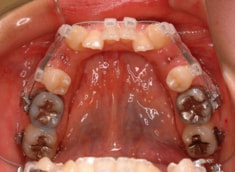

治療前

治療開始時